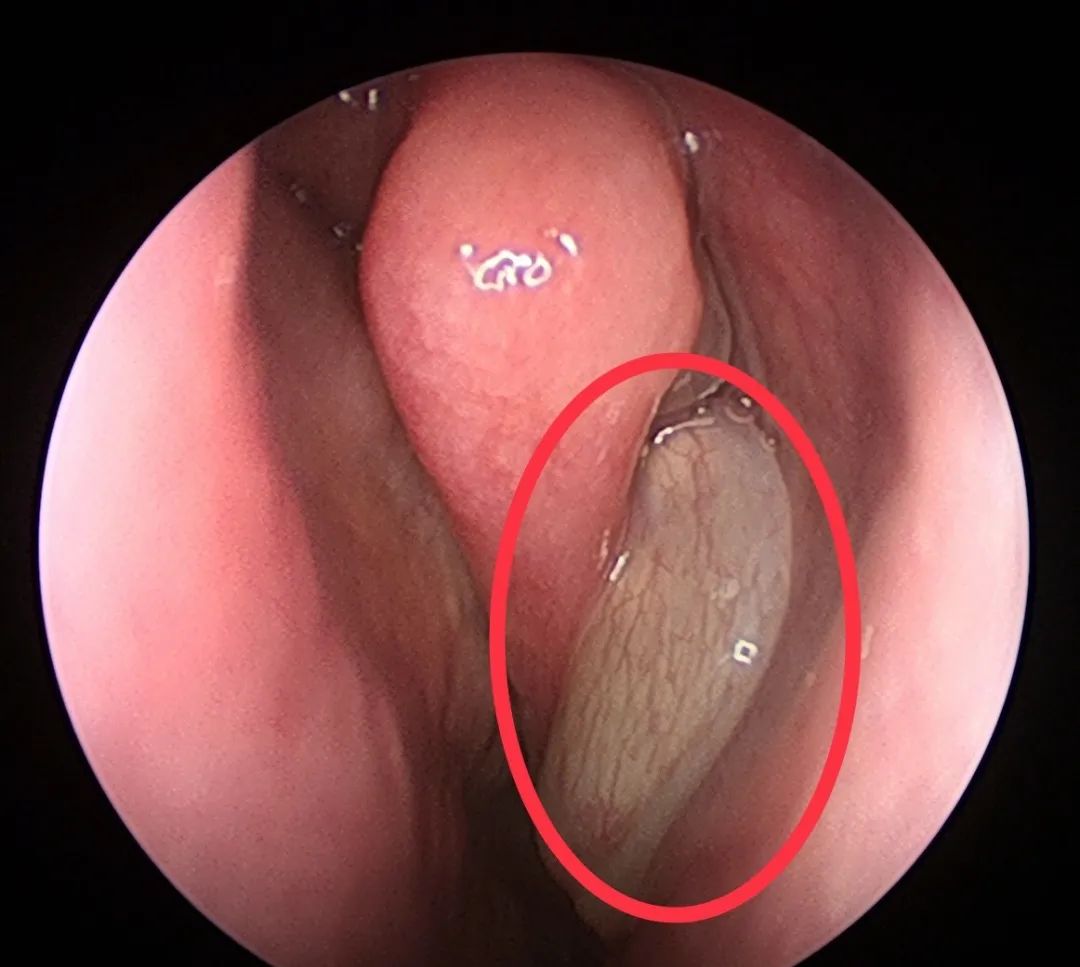

既然这多人都那么怕鼻息肉,那么真正的鼻息肉是啥样子的呢?

下面,我们来看看真正鼻息肉的面目:

其实,鼻息肉之所以让人们觉得那么恐怖,是因为它难以治根,经常复发。近年来,随着鼻内镜微创手术的开展,手术的效果还是不错的。